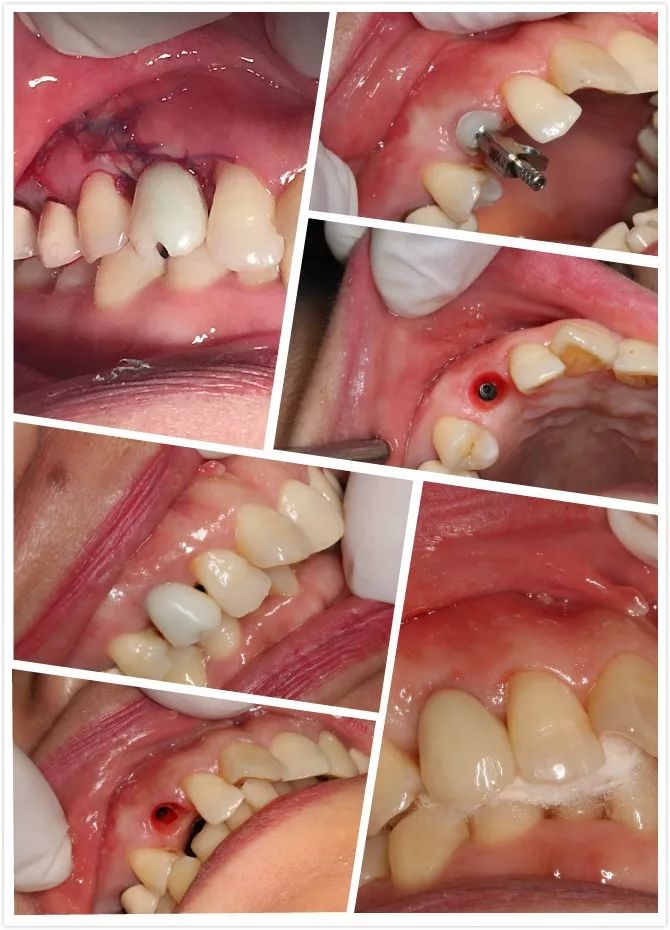

1 讲师简介 梁光强老师 (毕业于首都医科大学) 2 课程安排 第一天 1、口腔种植的基本概念 2、口腔门诊开展简单种植应该了解的基础知识 3、拓展种植牙业务医患交流技巧 4、民营口腔如何开展种植牙项目 5、开展种植所需要的设备,耗材以及所需要的准备工作 6、种植体的表面处理 7、如何读懂X光片 8、种植术前的评估--步骤与方法 9、缝合原则 10、{实习操作}缝合练习,种植X片的现场评估 第二天 1、种植牙手术术前准备 2、种植牙术中,术后的注意事项 3、种植手术植入流程 4、修复方式选择 5、印模技术 6、种植二期上部结构修复 7、门诊观看种植牙手术 8、{实习操作}种植植入模型实际操作 第三天 1、种植牙修复的并发症及处理方式 2、简单上颌窦提升技术 3、即刻种植 4、{实习操作}种植修复二期取模实际操作 3 病例展示 病例一 4 招生信息 主题:《走进民营-快速开展种植牙》 时间:2022年3月8日—3月10日 地点:宗言公司 主讲:梁光强老师 费用:老学员3600元/人(不含税)新学员3800元/人(不含税) 主办方:宗言牙材 注:公司站学习免费提供食宿 专车接送 长按二维码关注我们 更多精彩内容尽在 www.zongyan.com